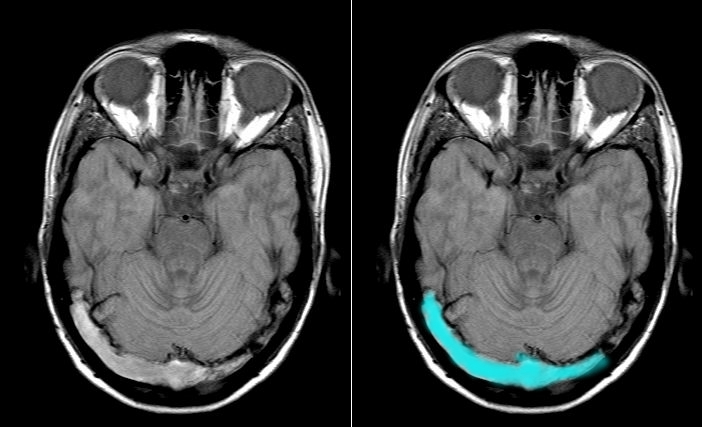

MRI Brain (Parenchymal Imaging)

Performed alongside MRV to assess consequences of thrombosis.

Findings:

- Venous infarction: Non-arterial distribution, often haemorrhagic

- Bilateral parasagittal (SSS)

- Temporal lobe (transverse sinus)

- Thalamic (deep veins)

- Haemorrhage: Petechial or confluent

- Oedema: Cytotoxic (restricted diffusion on DWI) and vasogenic

- Mass effect: Midline shift, herniation risk

Sequences:

- T1: Thrombus may be hyperintense (subacute)

- T2/FLAIR: Oedema, infarction

- DWI: Variable restriction (venous infarcts less restricted than arterial)

- GRE/SWI: Haemorrhage highly visible

- T1 post-contrast: Empty delta sign